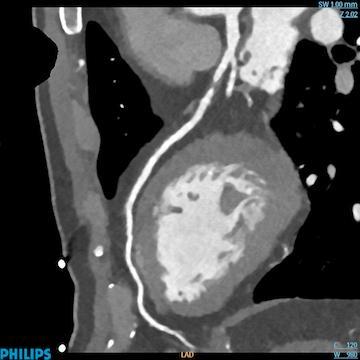

The suggested CAD-RADS classification is applied on a per-patient basis and represents the highest-grade coronary artery lesion documented by coronary CTA. It ranges from CAD-RADS 0 (zero) for the complete absence of stenosis and plaque to CAD-RADS 5 for the presence of at least one totally occluded coronary artery, and should always be interpreted in conjunction with the impression found in the report. Specific recommendations are provided for further management of patients with stable or acute chest pain based on the CAD-RADS classification.